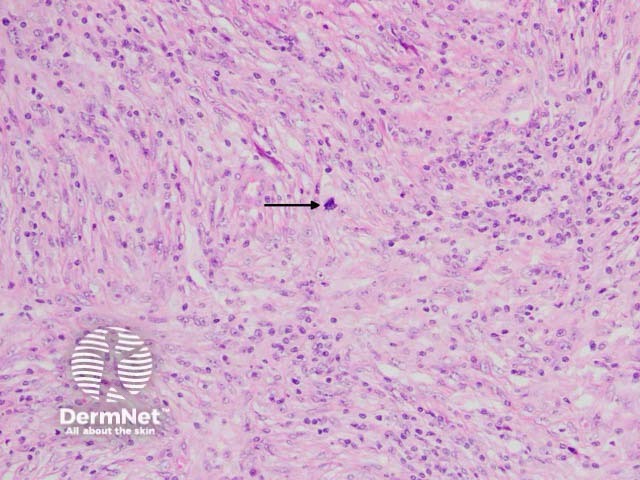

Histologically, the lesion is based in the dermis and seen underlying a normal epidermis (figure 1). The tumour is composed of an admixture of spindle-shaped and ovoid cells with a prominent inflammatory infiltrate (figures 2–3). The infiltrate is characteristically rich in plasma cells (best seen in figure 2). There may be some pleomorphism of the tumour cells and some mitotic figures (figure 3, arrow).

Figure 3